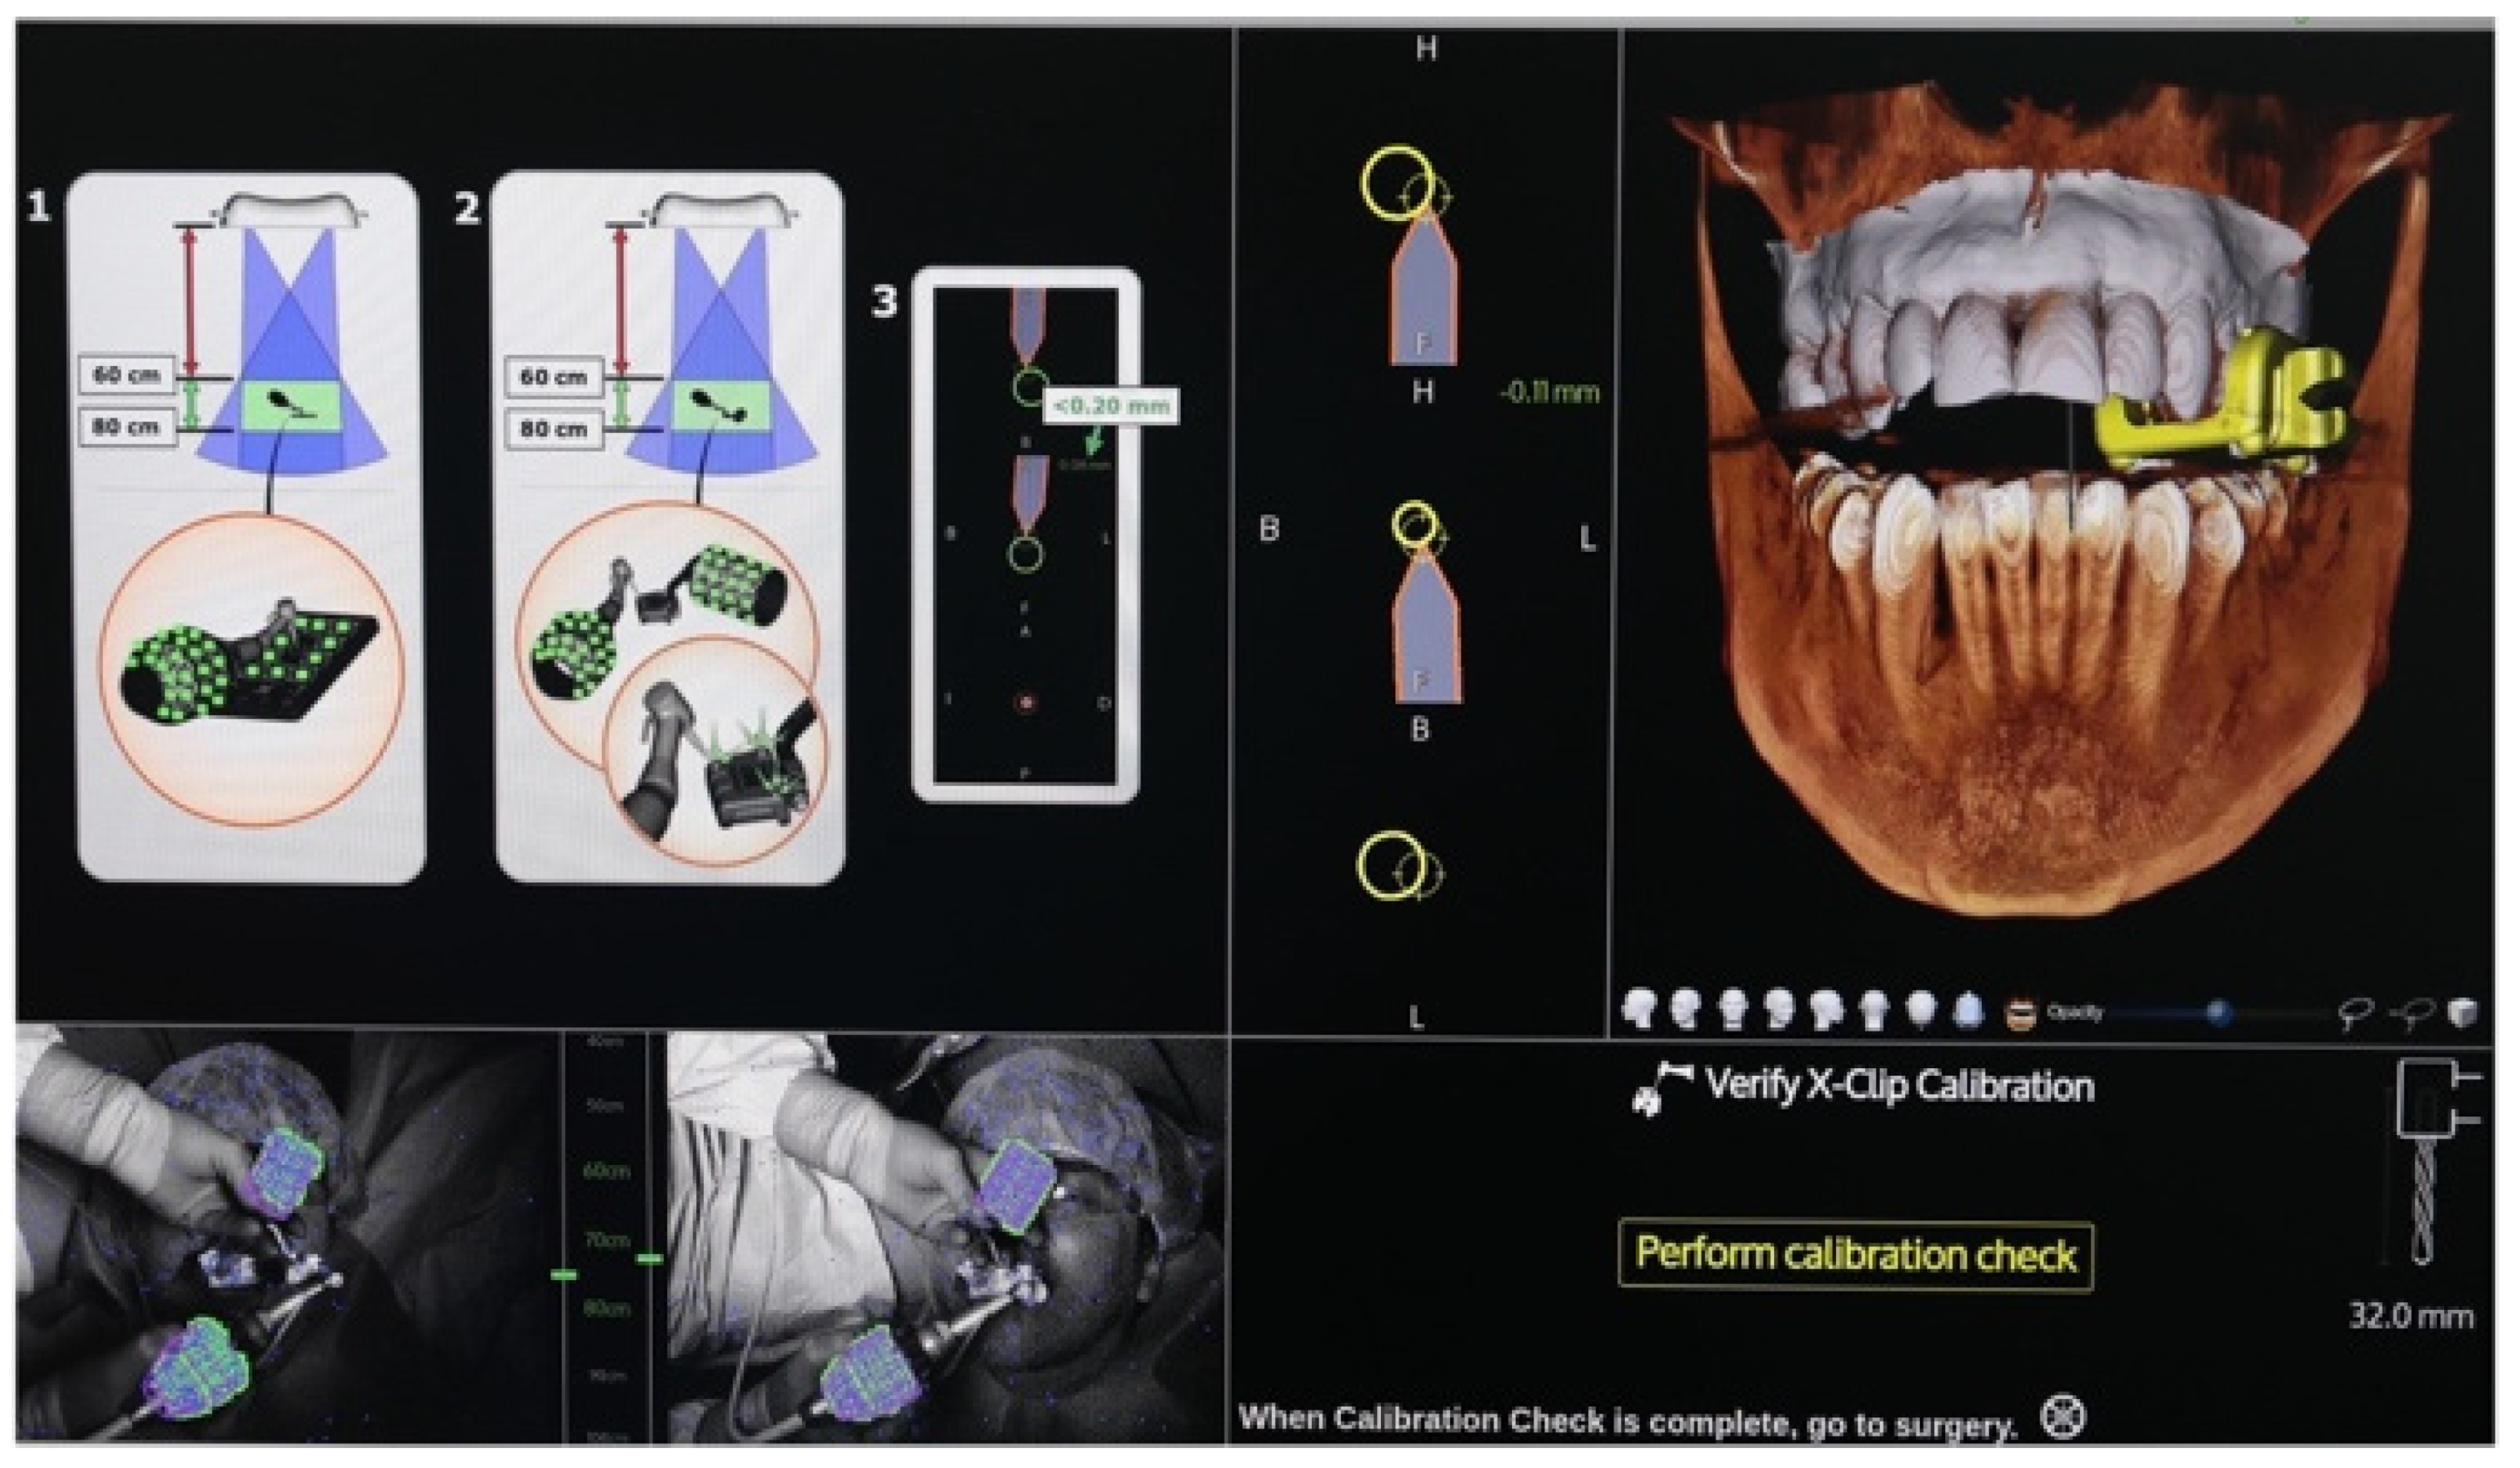

Calibration In Dynamic Navigation Surgery In Implamt

Browse our specialized Calibration In Dynamic Navigation Surgery In Implamt portfolio with numerous expertly curated photographs. optimized for both digital and print applications across multiple platforms. providing reliable visual resources for business and academic use. Each Calibration In Dynamic Navigation Surgery In Implamt image is carefully selected for superior visual impact and professional quality. Perfect for marketing materials, corporate presentations, advertising campaigns, and professional publications All Calibration In Dynamic Navigation Surgery In Implamt images are available in high resolution with professional-grade quality, optimized for both digital and print applications, and include comprehensive metadata for easy organization and usage. Our Calibration In Dynamic Navigation Surgery In Implamt collection provides reliable visual resources for business presentations and marketing materials. Whether for commercial projects or personal use, our Calibration In Dynamic Navigation Surgery In Implamt collection delivers consistent excellence. The Calibration In Dynamic Navigation Surgery In Implamt archive serves professionals, educators, and creatives across diverse industries. Regular updates keep the Calibration In Dynamic Navigation Surgery In Implamt collection current with contemporary trends and styles. Advanced search capabilities make finding the perfect Calibration In Dynamic Navigation Surgery In Implamt image effortless and efficient. Multiple resolution options ensure optimal performance across different platforms and applications.